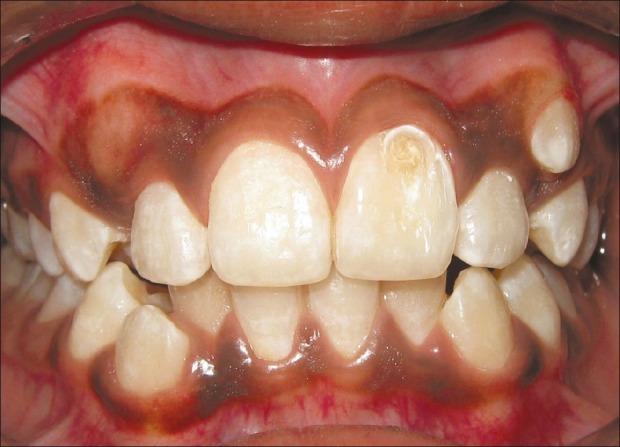

Talon cusp is a relatively uncommon developmental anomaly characterized by cusp-like projections, usually presenting on palatal/lingual surface of the anterior teeth. This cusp resembles an eagle's talon, and hence the name. Normal enamel and dentin covers the cusp, which may or may not contain an extension of pulp. Presence of this anomalous cusp on the facial surface of an anterior tooth is a rare finding and very few cases have been reported in the literature. In most instances, such cusps are associated with clinical problems such as poor esthetics and caries susceptibility. Management of such cases requires a comprehensive knowledge of the clinical entity as well as the problems associated with it. This case report presents a facial talon cusp on the maxillary left central incisor of a 10 year old boy, which was conservatively treated. Vitality of the affected tooth was maintained and followed up for a period of 1 year.